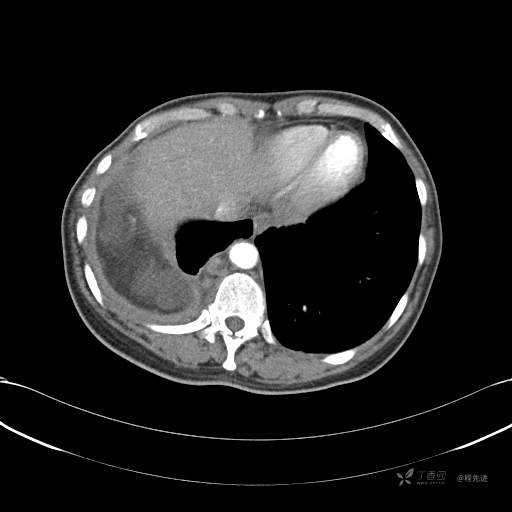

患者性别:女

患者年龄:51岁

简要病史:胸闷半年

肺淋巴管肌瘤病 (7)

乳糜胸 (8)